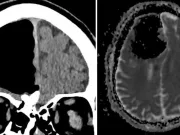

Acestui bărbat i-a „dispărut o bucată de creier” dintr-un motiv foarte ciudat

Atunci când un bărbat de 84 de ani din Irlanda s-a prezentat la medic cu plângeri de instabilitate, echipa medicală a descoperit un motiv...